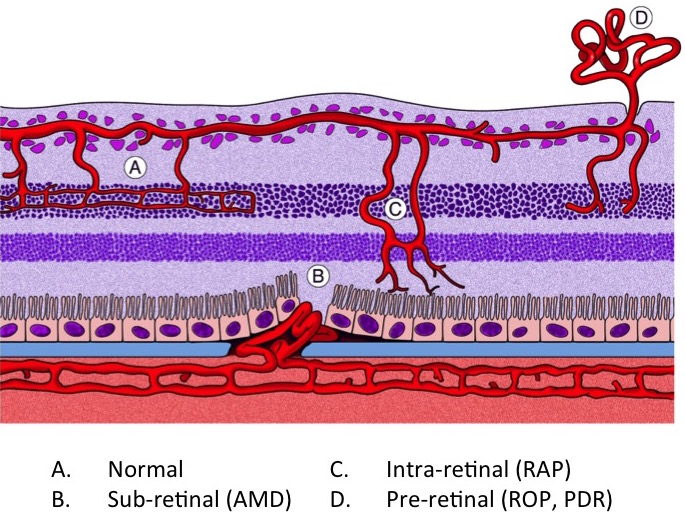

Neovascularization Assessment

Neovascular area can be assessed for both the OIR and LCNV models. We carefully dissect the retina or choroid, stain for blood vessels, and flat-mount the tissue. We then measure neovascular growth using computer-assisted image analysis tools. Our methods allow for precise and highly reproduceable data.